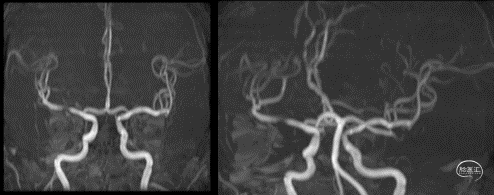

入院影像检查

MRI+DWI

重要影像结论:右侧放射区、右侧基底节区、左侧额叶近大脑镰处多发急性梗死。

重要影像结论:右侧颈内动脉岩骨段管腔内不清晰,眼动脉段远端管腔较对侧明显缩小。

MRA

重要影像结论:右侧大脑中动脉M1段局限性狭窄。

DWI

重要影像结论:右侧额颞枕顶叶多发急性期脑梗死灶。